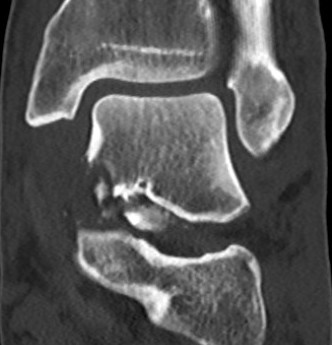

Xray / CT

Ensure no displacement / malalignment

Anatomical reduction + fixation

1. Remove loose bodies from subtalar joint

2. Reduction - avoid varus and shortening medial neck

- often medial comminution

Canale view

- evaluates talar neck

- foot everted 15 deg

- look for medial shortening / varus

Xrays

| AP | Lateral | Canale View |

|---|---|---|

| Entry point of the screws |

Evaluate neck reduction

|

Evaluates the neck reduction |

Lateral off articular surface Medial through articular cartilage |

Depth of screws |

Beam angled 75o to foot Foot 15o pronated |